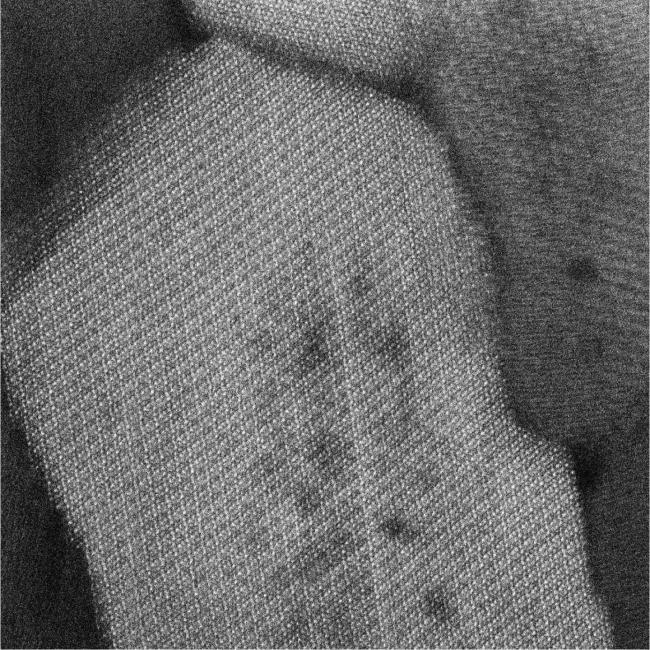

An imaging technique called scanning transmission electron microscopy (STEM) has provided scientists with some rough pictures of enamel crystallites. However, the intensity of traditional STEM beams required for a clearer view would damage the enamel before a picture could be generated.

In new research, a team led by Karen DeRocher, Dr. Paul Smeets, and Dr. Derk Joester from Northwestern University used a combination of imaging techniques to produce a picture of enamel down to the atomic level. These techniques include a version of STEM performed at very cold temperatures and atomic probe tomography, which takes pictures of substances one layer of atoms at a time.

The methods revealed a high-definition view of the crystallites, which are made mostly of a mineral known as hydroxylapatite. They also revealed the patterns in which other minerals were deposited within the crystals, including magnesium, sodium, and fluoride.

Atomic-level 3D image reconstructions showed that these other minerals tended to be found inside the core of the crystallites rather than in the outside layer, or shell. Computer modeling suggested that the minerals in the core contribute to their profound strength.